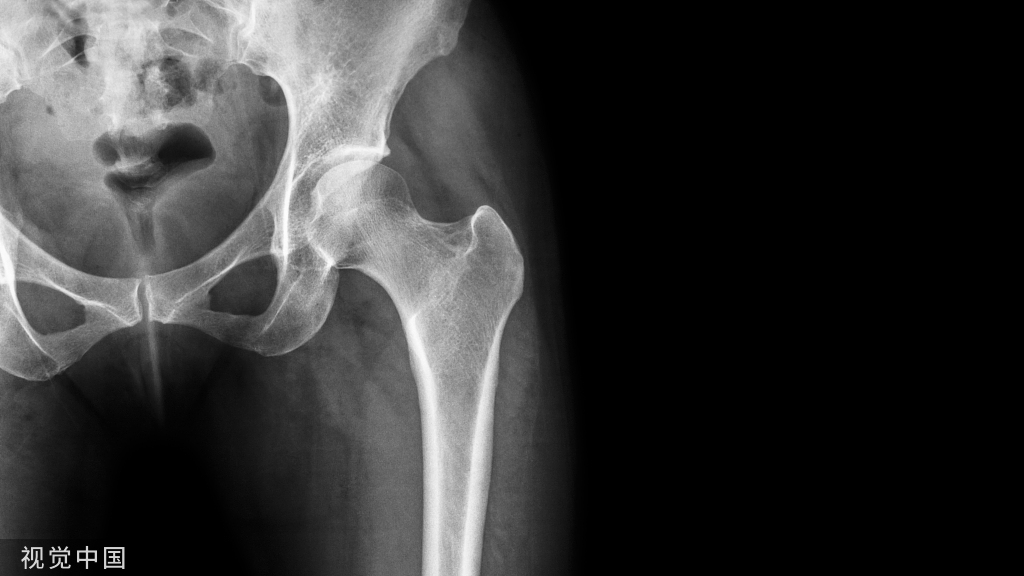

影像诊断:部分Hoffa骨折X线片不能提供明确的诊断,漏诊率较高。需要CT或MRI检查,并根据患者的病史、查体及影像学检查予以确诊。

部分Hoffa骨折普通X光片易漏诊

CT扫描在矢状位、轴位容易发现骨折及骨折线的走形方向

MRI不但可发现隐匿性骨折,还可发现合并的软组织损伤